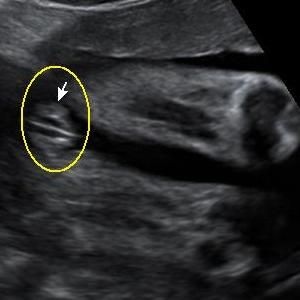

• A simple google search can answer your question. I pulled these from google:

Three lines = girl

Twig and berries = boy